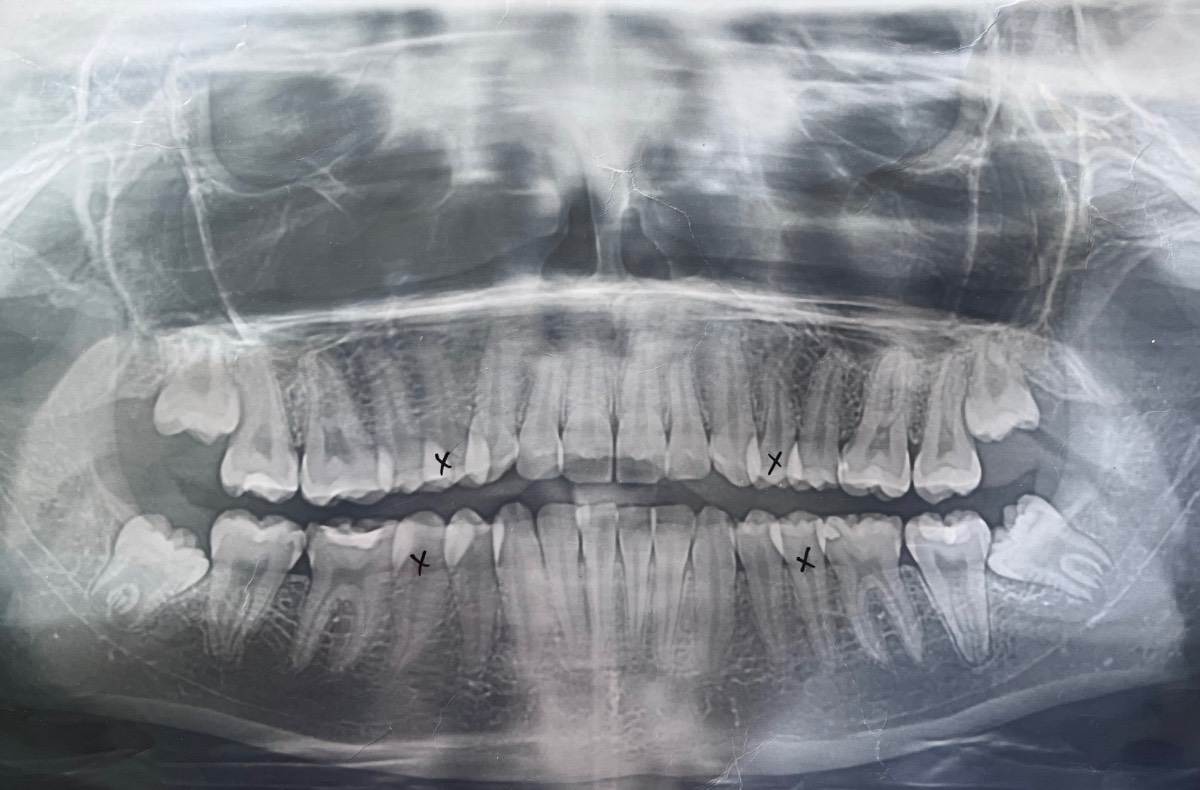

Мне 17 лет, я хочу поставить брекеты. У меня на нижней челюсти скученность зубов, на верхней протрузия (зубы передние отклонены вперед на 2-3 градуса). Прикус в норме. Удаляла 1 зуб мудрости внизу, 2 месяца назад, потому что очень давил на зубной ряд, и вот сейчас решила заняться брекетами. Пошла к одному ортодонту - сказал что наверху никакие удалять не надо, они никак не мешают, только нижний зуб мудрости, второй удалить, и то позже. Прихожу к другому ортодонту, говорит что надо удалять 5-ые зубы — 2 сверху, 2 снизу, ибо по другому не исправить ситуацию, без удаления им не будет места и они из кости вылезут просто.. очень нужен совет, какие зубы удалять? Фото снимков и слепков нижеIMG_5334.jpeg.b29acf03abb1dd3861d2f5c50d9defed.jpegIMG_5337.jpeg.05a95352e4a6439f90f8c35cb28336e8.jpegIMG_5338.jpeg.863efa671750d73ce517a3979f6646cb.jpegIMG_5336.jpeg.af01d9033016196d4046949a804ccd63.jpegIMG_5335.jpeg.0f2aaff927e30a409e8f5bb173a1dede.jpeg